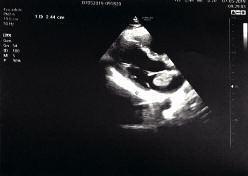

261 Riscontro ecocardiografico di mixoma atriale durante la valutazione dell’idoneità cardiologica ai fini del reclutamento in Forza Armata

E ch o c a r d i o g r a p h i c e v i d e n c e o f a t r i a l m y x o m a d u r i n g t h e assessment of cardiological suitability for recruitment into the Armed Force

Le visite di idoneità concorsuale, al pari di quelle arruolative all’epoca della leva, possono fungere da screening della popolazione giovane Il riscontro di anomalie congenite o acquisite, spesso misconosciute, può evitare conseguenze sanitarie gravi per il candidato, particolarmente in campo cardiologico